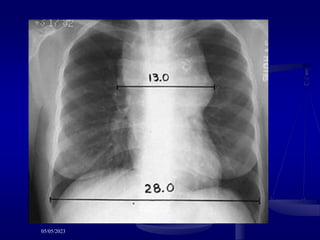

 Criteria for bulk

 10 cm nodal mass

 mediastinal mass > 1/3 thorax diameter

 Bulky lymphadenopathy >6cm/ bulky mediastinum

>1/3 of intra-thoracic diameter.

 mediastinal mass with tumor diameter is > 1/3 maximal thoracic diameter